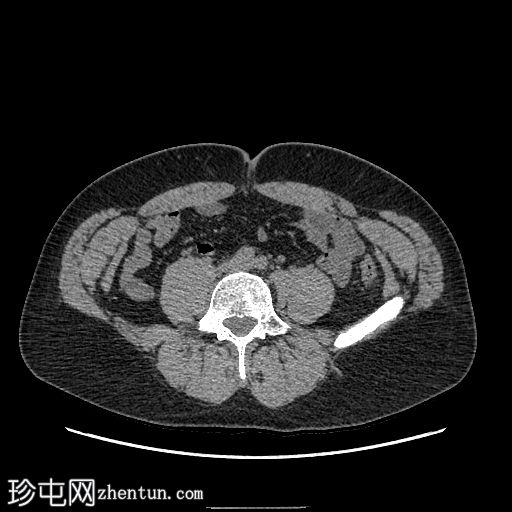

腹部及盆腔CT

CT

轴位

平扫

左下腹降结肠旁可见卵圆形脂肪密度影,边缘密度略高,邻近脂肪组织呈条索状改变(冠状位和矢状位)。

未见肾结石或输尿管结石。

未见腹腔内游离气体或液体。